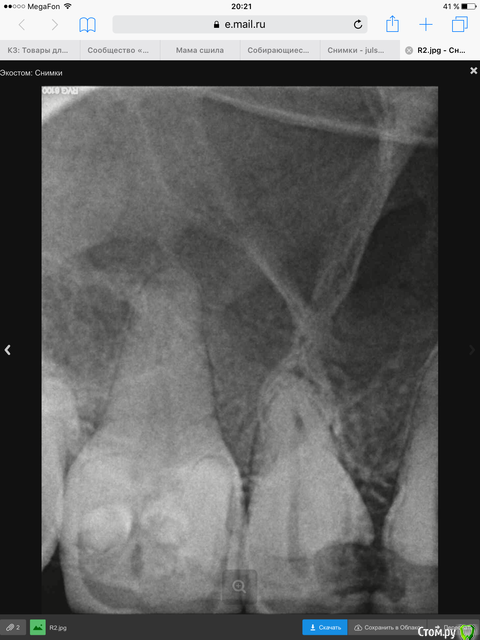

Julsvs Опубликовано 30 марта, 2016 Автор Поделиться Опубликовано 30 марта, 2016 Вот как смогла сфотографировала. 1 Ссылка на комментарий

Julsvs Опубликовано 13 мая, 2016 Автор Поделиться Опубликовано 13 мая, 2016 Вот КТ( проблема в правой шестерке). Другого снимка нет- выдали результаты на диске. Ссылка на комментарий

Doctor Vlad Опубликовано 13 мая, 2016 Поделиться Опубликовано 13 мая, 2016 это снова опг получилось. окно в программе наведите на 16 15 зубы и срезы тоже выложите 1 Ссылка на комментарий

DmitrySH Опубликовано 13 мая, 2016 Поделиться Опубликовано 13 мая, 2016 Мелковат снимок. Да, там есть изменения вокруг шестерки. Может на КТ там что-то еще можно увидеть. Но если судить по этому снимку, то зуб подлежит эндодонтическому лечению. Для удаления сейчас нет поводов. 1 Ссылка на комментарий

Doctor Vlad Опубликовано 14 мая, 2016 Поделиться Опубликовано 14 мая, 2016 вижу периодонтит! пародонтита не вижу 1 Ссылка на комментарий